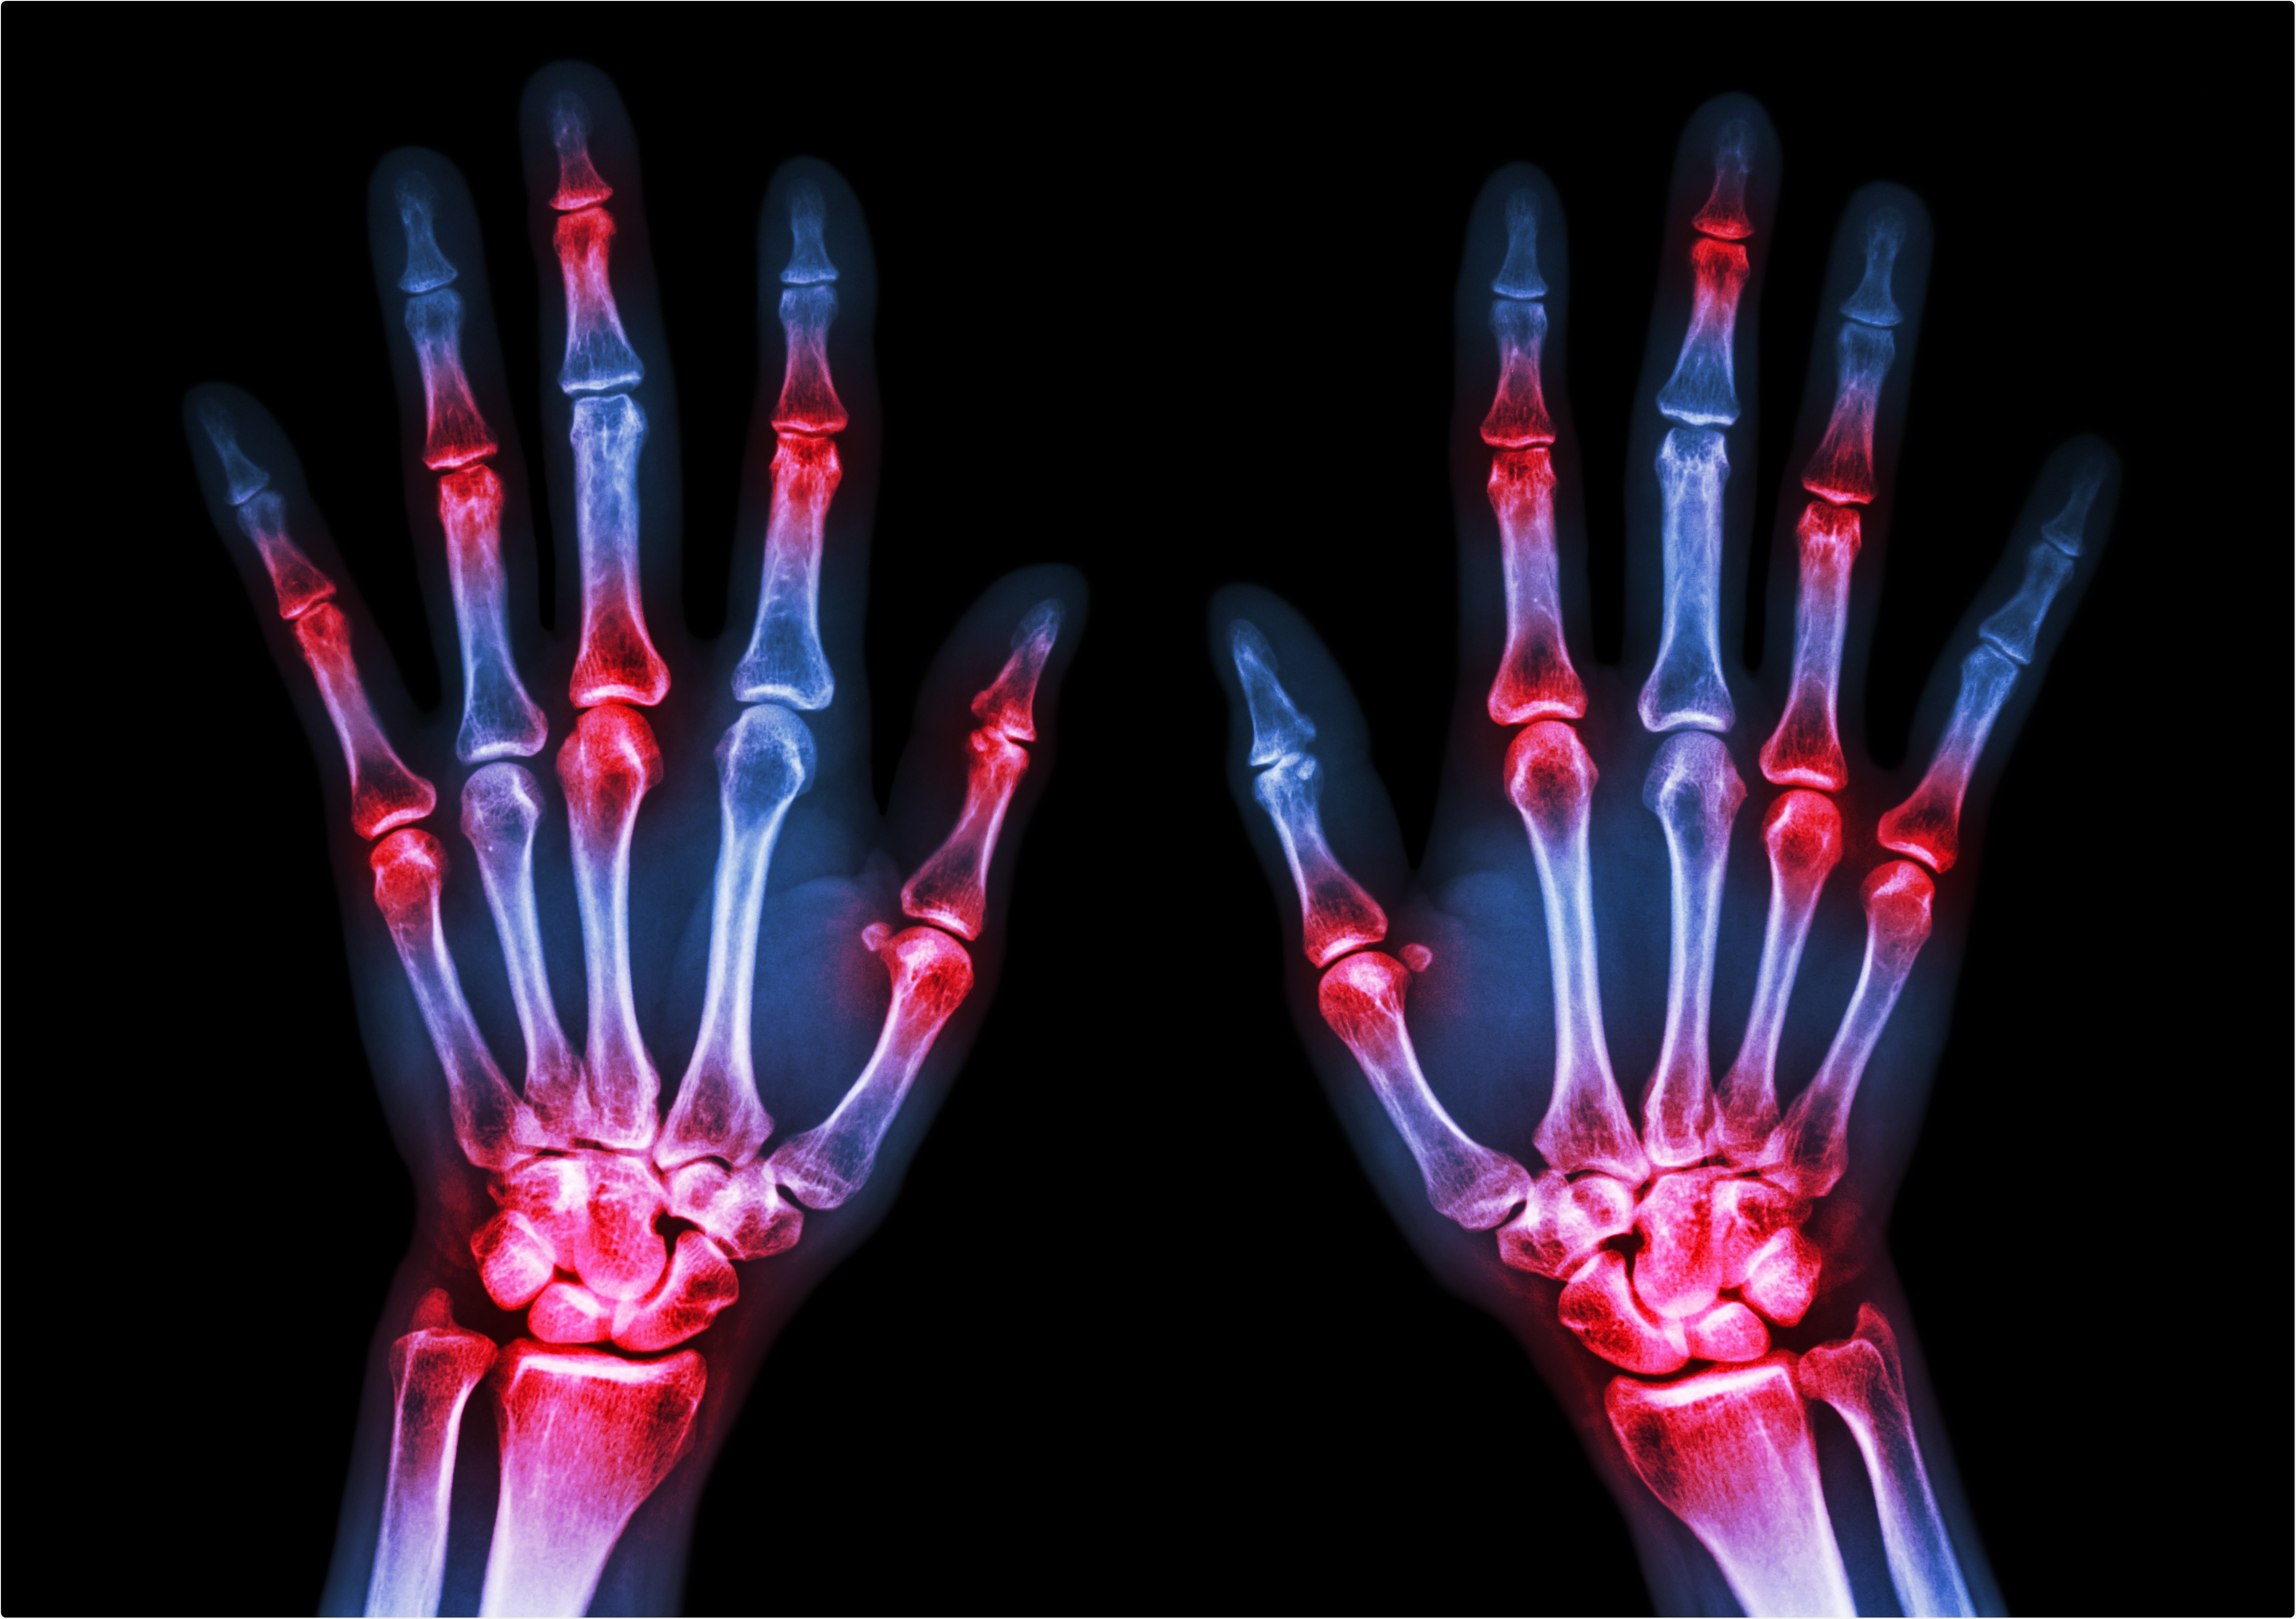

Rheumatoid arthritis is a T-cell and B-cell mediated autoimmune disease that, again, targets the joints.

The condition is characterized by high circulating levels of TNF-α and IL-6, and, like gout, could potentially lead to an increased immune response to SARS-CoV-2. Rheumatoid arthritis is also associated with a greater risk of cardiovascular disease.